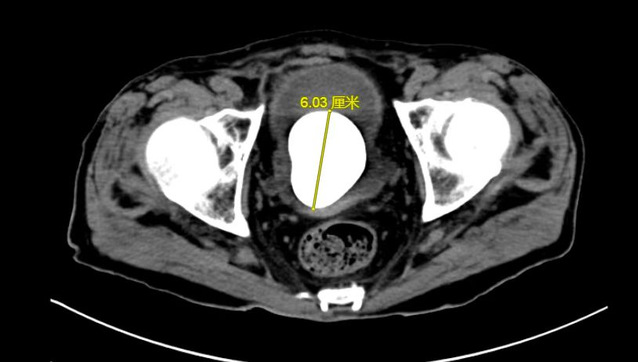

数月来,徐老伯常有尿频尿痛症状,由于近期症状明显加重,甚至出现反胃、食欲不振致使精神萎靡的情况,在当地医院就诊时,被查出膀胱内有一枚6cm*5cm大小的膀胱结石。

由于徐老伯已经84岁了,手术风险高,辗转多家医院没有得到合适的治疗方案。家属推着轮椅上的徐老伯来到了苏州九院泌尿外科门诊上,主任医师陈建春仔细询问病史及阅片后,第一时间将患者收入病房。经过详尽的检查,陈建春团队发现患者精神萎靡部分原因是由于患者营养状态差导致,联合营养科为患者制定了提高营养状态的治疗方案。

目前,治疗膀胱结石的主流手段为经尿道钬激光碎石术,但考虑到患者高龄,且营养状态虽较前好转,但仍较正常老年患者不足,若采取经尿道手术治疗患者“鹅蛋”大小的膀胱结石,患者难以耐受3小时甚至更长时间的手术及麻醉过程,因此,在与患者沟通后,陈建春团队选择了传统的膀胱切开取石术。最终,在手术麻醉、ICU及护理团队的共同协作下,陈建春主任团队顺利将“鹅蛋”大小的膀胱结石自患者体内取出,整个手术过程仅用30分钟。